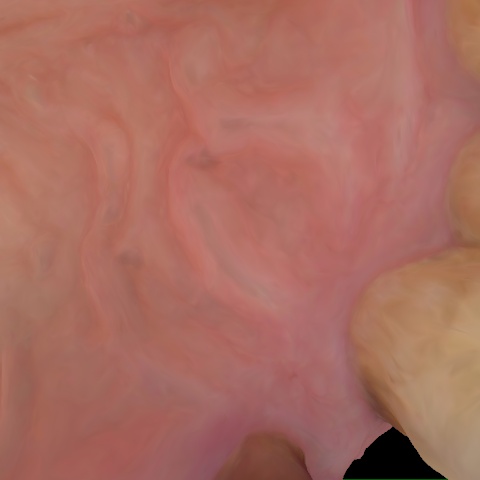

Annotated as "Good"